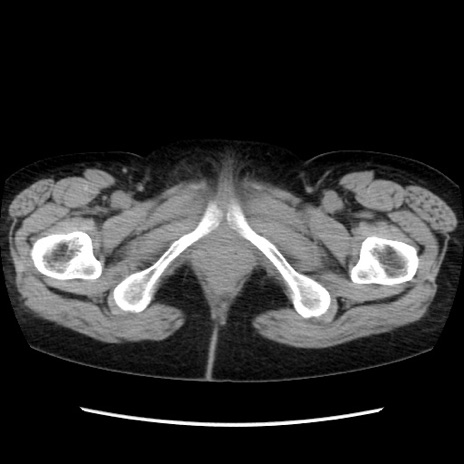

症例32(横断像)

【症例】40歳代 女性

【主訴】上腹部痛、嘔気・嘔吐

【現病歴】約9時間前頃から急に上腹部痛、嘔気、嘔吐が出現。改善しないため救急要請。

【既往歴】子宮頚癌(広汎子宮全摘術、放射線療法)、腸閉塞

【身体所見】腹部:平坦、軟、腸雑音亢進、上腹部を中心に腹部全体に圧痛あり。

【データ】WBC 8400、CRP 0.03